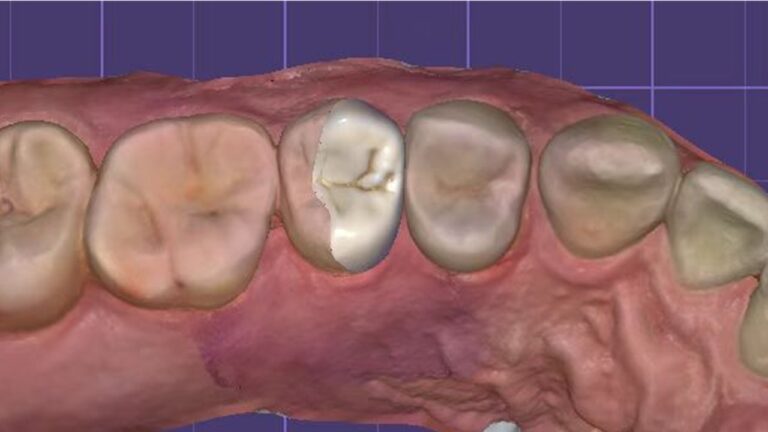

Inlays and Onlays

Inlay restoration refers to a fixed restoration method that uses custom-made restorations to precisely repair damaged areas of the tooth in order to restore the tooth’s shape and function.

Common Forms: Ordinary inlays, high inlays, veneer inlays that cover more cusps, or partial crown restorations.

Indications:Restorative scenarios involving moderate to extensive tooth structure loss, or defects affecting the proximal and occlusal surfaces of posterior teeth, where the remaining tooth structure retains sufficient salvage value.